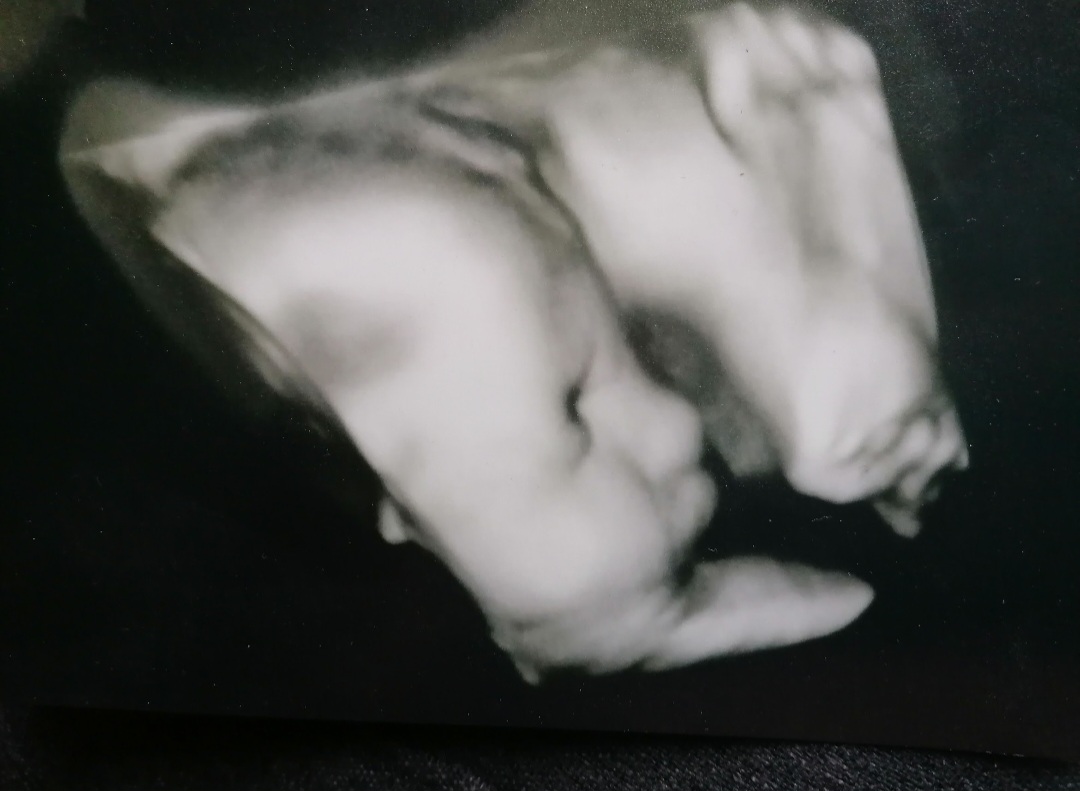

Sinulla on erityinen tehtävä. Sinusta on tulossa äiti erityiselle vauvalle. Onnittelen sinua ihanasta ja niin rakkaasta vauvasta, ja lämmin halaus kaikkeen siihen, mitä juuri nyt käyt läpi. Tiedän, että on paljon läpikäytävää ja valtava määrä monenlaisia tunteita, mutta haluan sanoa sinulle, että et ole yksin. Erityisen vauvan odotus on erityinen matka, ja olen täällä jos tarvitset matkallesi tukea ja jonkun, joka kulkee rinnallasi, kun kaikki on vasta alussa.